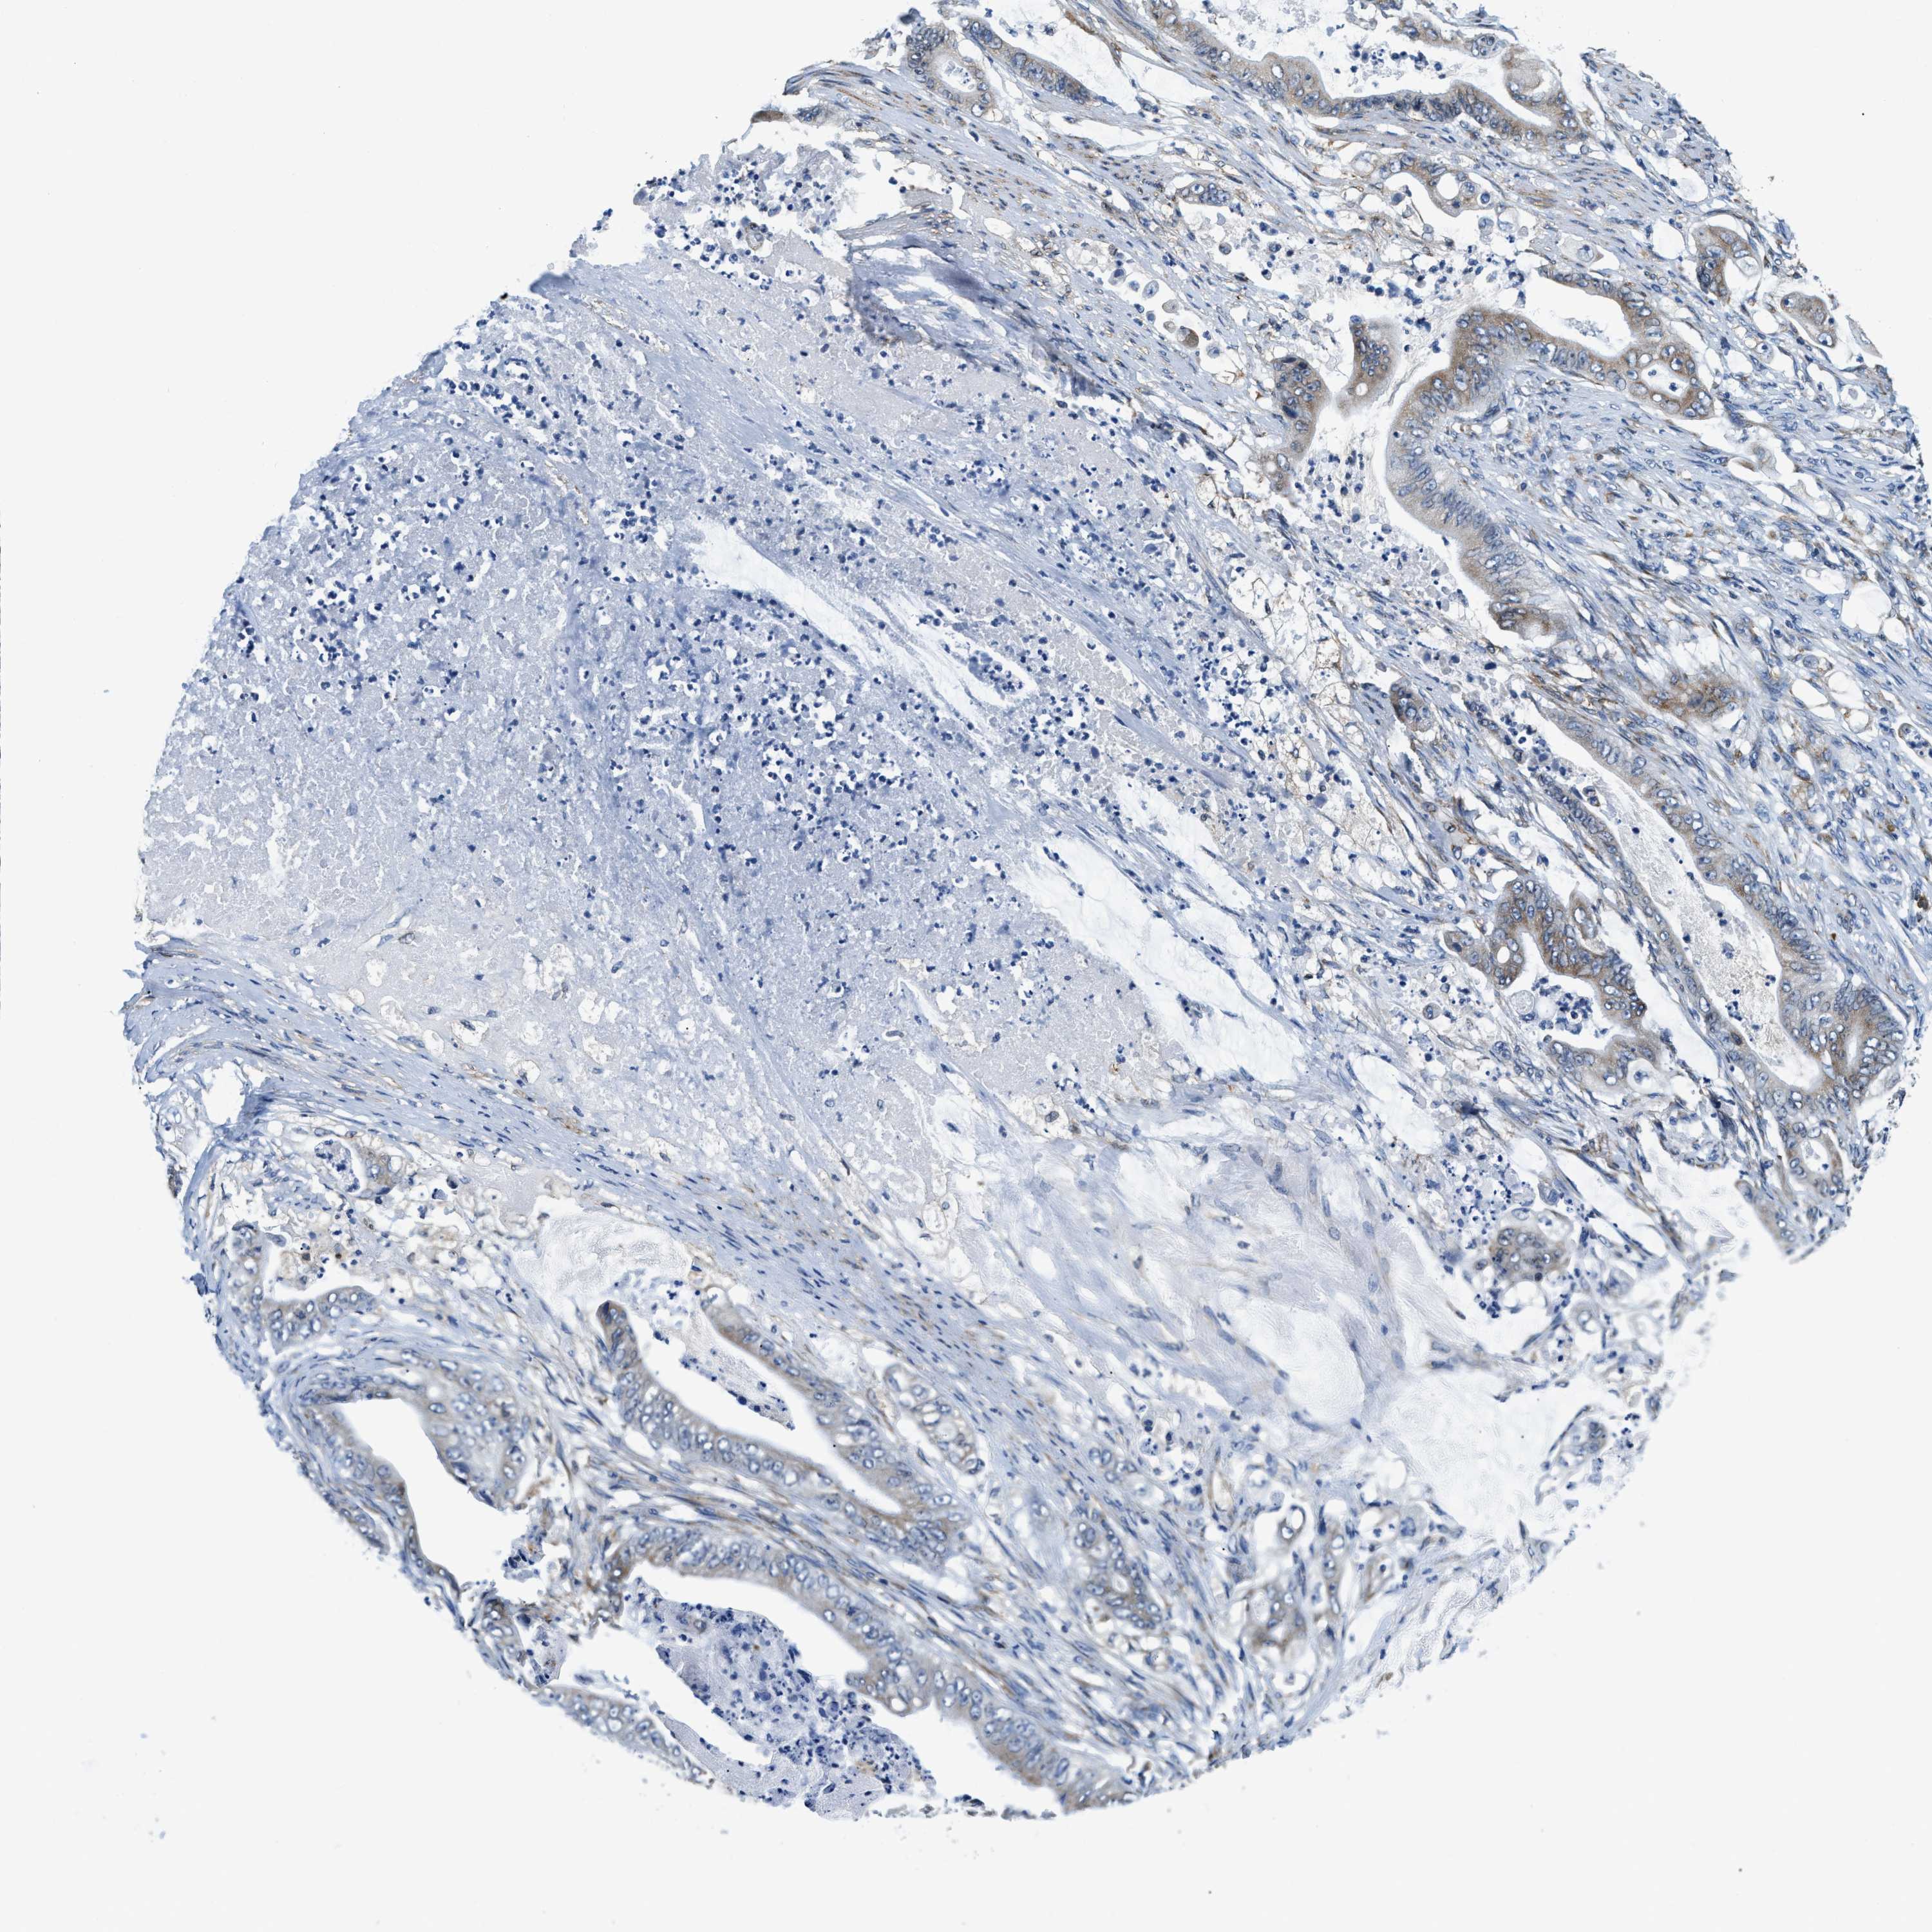

STOMACH CANCER - Protein expressioni

A mouse-over function shows sample information and annotation data. Click on an image to view it in a full screen mode. Samples can be filtered based on level of antibody staining by selecting one or several of the following categories: high, medium, low and not detected. The assay and annotation is described here.

Antibody stainingi

Antibody staining in the annotated cell types in the current human tissue is reported as not detected, low, medium, or high, based on conventional immunohistochemistry profiling in selected tissues. This score is based on the combination of the staining intensity and fraction of stained cells.

Each image is clickable and will lead to virtual microscopy that enables deeper exploration of all samples and also displays staining intensity scores, fraction scores and subcellular localization as well as patient and tissue information for each sample.

Antibody HPA019698

Staining

High

Medium

Low

Not detected

Intensity

Strong

Moderate

Weak

Negative

Quantity

>75%

75%-25%

<25%

None

Location

Nuclear

Cytoplasmic/membranous

Cytoplasmic/membranous,nuclear

Adenocarcinoma, NOS